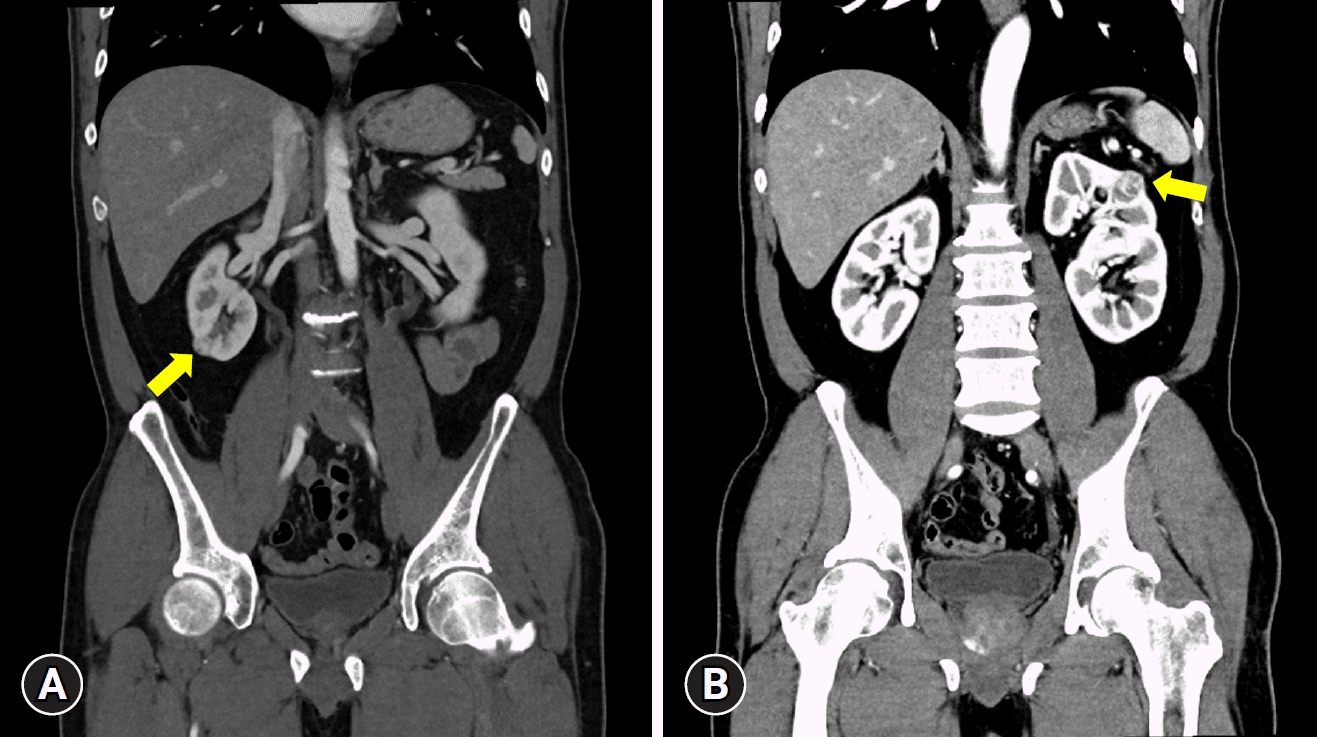

A 52-year-old man presents to the outpatient urology department with an incidentally discovered bilateral kidney mass by ultrasound. On the abdominal computed tomography (CT), the masses measured 1.5 cm on the right and 2.0 cm on the left. The RENAL (radius, exophytic/endophytic, nearness to collecting system or sinus, anterior/posterior, and location relative to polar lines) nephrometry score was 5 for both sides the PADUA (preoperative aspects and dimensions used for an anatomical) score was 7 for the left and 8 for the right sides (Fig. 1). The patient had no previous history of surgery or trauma and no history of comorbidities or medications. Preoperatively, serum creatinine and estimated glomerular filtration rate (eGFR) were 0.81 mg/dL and 86.7 mL/min/1.73 m2, respectively. All other preoperative laboratory findings were within normal limits. His body mass index was 24.3 kg/m2. Given the relatively small size of the masses, a preoperative biopsy was not performed.

Fig. 1.

The coronary images on preoperative computed tomography show (A) a 1.5-cm right and (B) a 2.0-cm left endophytic mass (arrows).